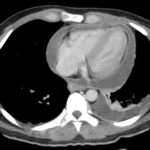

Pericarditis

This 33 male patient gave a history of recent travel 3 months of fevers, shoulder tip pain,...

Pneumopericardium

Air appears around heart but does not extend above great vessels

Air in the...